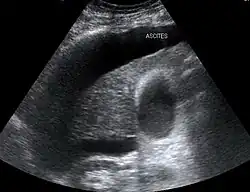

Estão descritas duas formas de síndrome hepatorrenal: o "tipo 1" envolve um declínio rapidamente progressivo da função renal, enquanto o "tipo 2" está associado a ascite (acumulação de líquido no abdómen) que não melhora apesar da administração de medicamentos diuréticos padrão. O risco de morte na síndrome hepatorrenal é muito elevado: a mortalidade dos indivíduos que apresentam "tipo 1" é superior a 50% a curto prazo.[1]

Diferente da síndrome hepatorrenal do tipo 1, que tem uma evolução rápida, a do tipo 2 tem início e progressão bem mais lentos. Ela é definida por um aumento no nível de creatinina sérica em mais de 133 mmol/L (1,5 mg/dL) ou por uma depuração de creatinina inferior a 40 mL/min, e um sódio urinário menor que 10 mmol/L.[8] Ela também possui um prognóstico pobre, com uma sobrevida média de cerca de seis meses, a menos que seja feito um transplante de fígado no indivíduo afetado. A SHR do tipo 2 parece fazer parte de um espectro de doenças associadas com o aumento da pressão na circulação da veia porta, que se manifesta clinicamente com o acúmulo de líquido no abdome, a ascite. O espectro continua com uma ascite refratária a diuréticos, quando os rins não mais conseguem excretar sódio suficiente para eliminar líquido mesmo com o uso de medicamentos diuréticos. Muitos pacientes com a SHR do tipo 2 tem uma ascite com essas características antes de desenvolverem a deterioração da função renal.[9]

Os dois tipos da síndrome hepatorrenal partilham três fenômenos principais: função do fígado alterada, anormalidades na circulação e insuficiência renal. Já que esses fenômenos não produzem de fato sintomas até o fim do curso da doença, os indivíduos que sofrem com esta síndrome geralmente são diagnosticados com base em exames laboratoriais alterados. A maioria das pessoas que desenvolvem SHR têm cirrose e por isso podem ter os mesmos sinais e sintomas desta doença, como icterícia, alteração do estado mental, nutrição prejudicada e a presença de ascite.[4] Especificamente, o surgimento de ascite, que é resistente ao uso de medicamentos diuréticos, é característica do tipo 2 de SHR. A oligúria, que significa uma diminuição no volume de urina, pode ocorrer como consequência da insuficiência renal. Todavia, alguns indivíduos com SHR continuam a produzir urina normalmente.[5] Como estes sintomas podem não aparecer, não são incluídos como critérios maiores ou menores para o diagnóstico desta condição. Invés disso, a doença é diagnosticada no indivíduo a partir de resultados de testes laboratoriais para a exclusão de outras causas.[5]